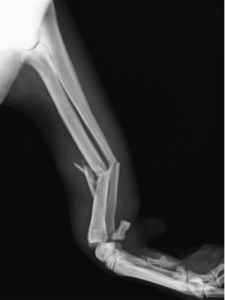

術前レントゲン

コメント;

撓尺骨遠位1/3での粉砕骨折であり、かつ遠位の骨片は粉砕骨折の安定に必要なスクリューの数を確保するのが困難なほど短いものであった。また、遠位には亀裂の存在も示唆された。